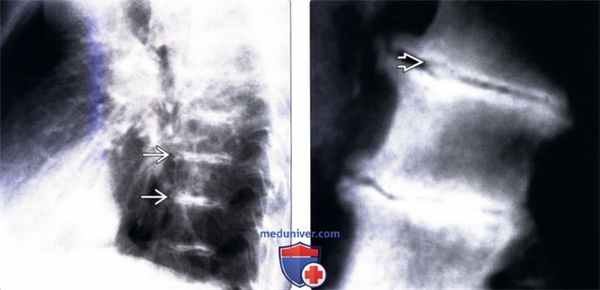

(Слева) Рентгенограмма грудного отдела позвоночника в боковой проекции: характерная кальцификация межпозвонковых дисков на всех уровнях. Обратите внимание на кальцинаты в межтеловых промежутках, а также на тяжелые дегенеративные изменения всех замыкательных пластинок.

(Справа) На рентгенограмме позвонков в боковой проекции в области межтелового пространства на фоне выраженного его дегенеративного сужения определяется кальцинат.

(Слева) На рентгенограмме поясничного отдела позвоночника в боковой проекции определяется выраженное снижение высоты и кальцификация межпозвонковых дисков. Передняя и задняя продольные связки также оссифицированые, напоминая картину анкилозирующего спондилита.

(Справа) На рентгенограмме поясничного отдела позвоночника в прямой проекции в дополнение к левосторонней дегенеративной сколиотической деформации определяется выраженное снижение высоты и кальцификация межпозвонковых дисков.